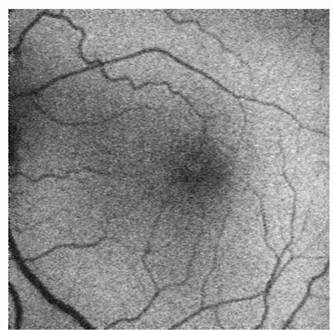

Вид глазного дна при отслойке стекловидного тела